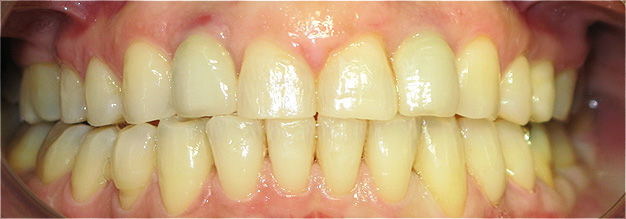

Resultado de colocação de implante dentário na Clínica São Filinto

Caso 8 - Colocação de implantes dentários para reabilitação com prótese fixa em zircónio cerâmica no 4º quadrante.

![]() |